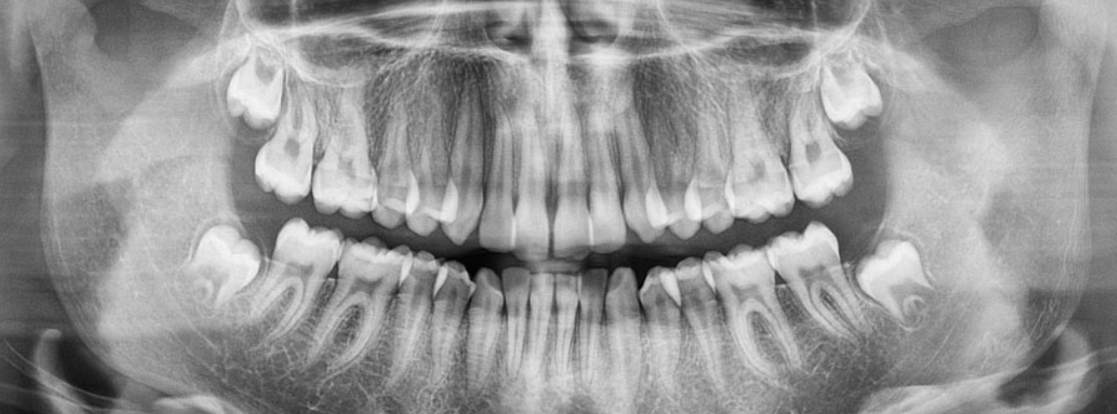

Vi använder sedan 2004 digital röntgenteknik. Fördelarna för dig som patient är att stråldosen reduceras med tre fjärdedelar jämfört med konventionell bildtagning. Bilden projiceras avsevärt snabbare i våra datorer och vi kan utläsa mer ur dessa bilder genom förstoring och kontraständring.

2014 har vi investerat i högupplösta bildsensorer med den senaste tekniken. Vi har möjlighet att ta helkäksbilder med en speciell röntgenapparat som heter ortopantomograf, OPG. Dessa bilder har stor betydelse vid planering av operationer i samband med implantatbehandlingar, uttagning av visdomständer, tandreglering samt vid kontroll av käkar och tänder där ”vanliga” bilder inte räcker till.